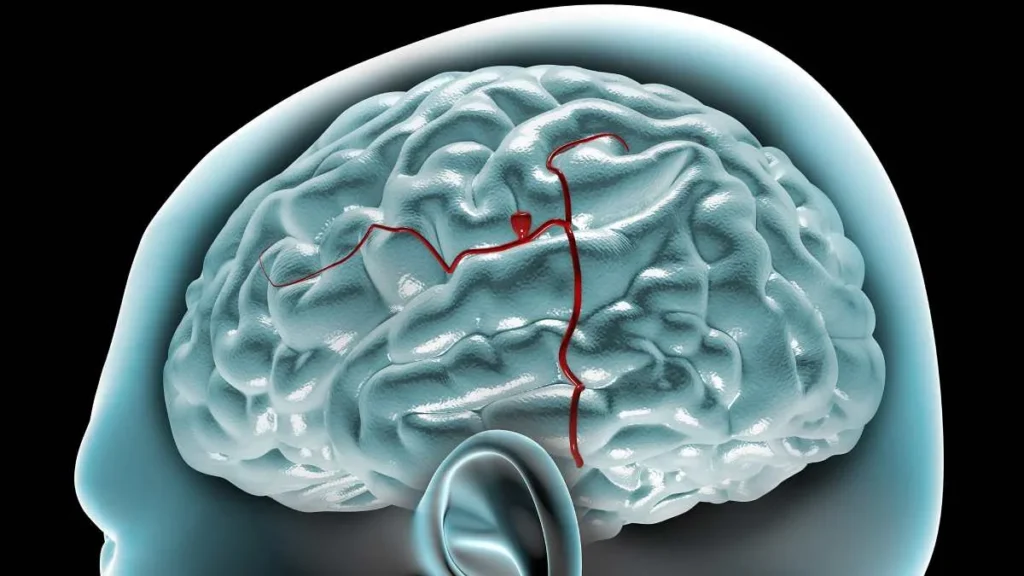

Aneurisma intracraneal

Los aneurismas saculares, comúnmente conocidos como aneurismas "berry", son dilataciones anormales en la pared de las arterias que suelen presentarse en las bifurcaciones arteriales. Esta predilección por las bifurcaciones se…